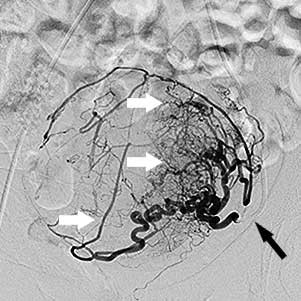

Ліва маткова артерія:

чорна стрілка - катетер, білі стрілки -

розширені артерії вузла